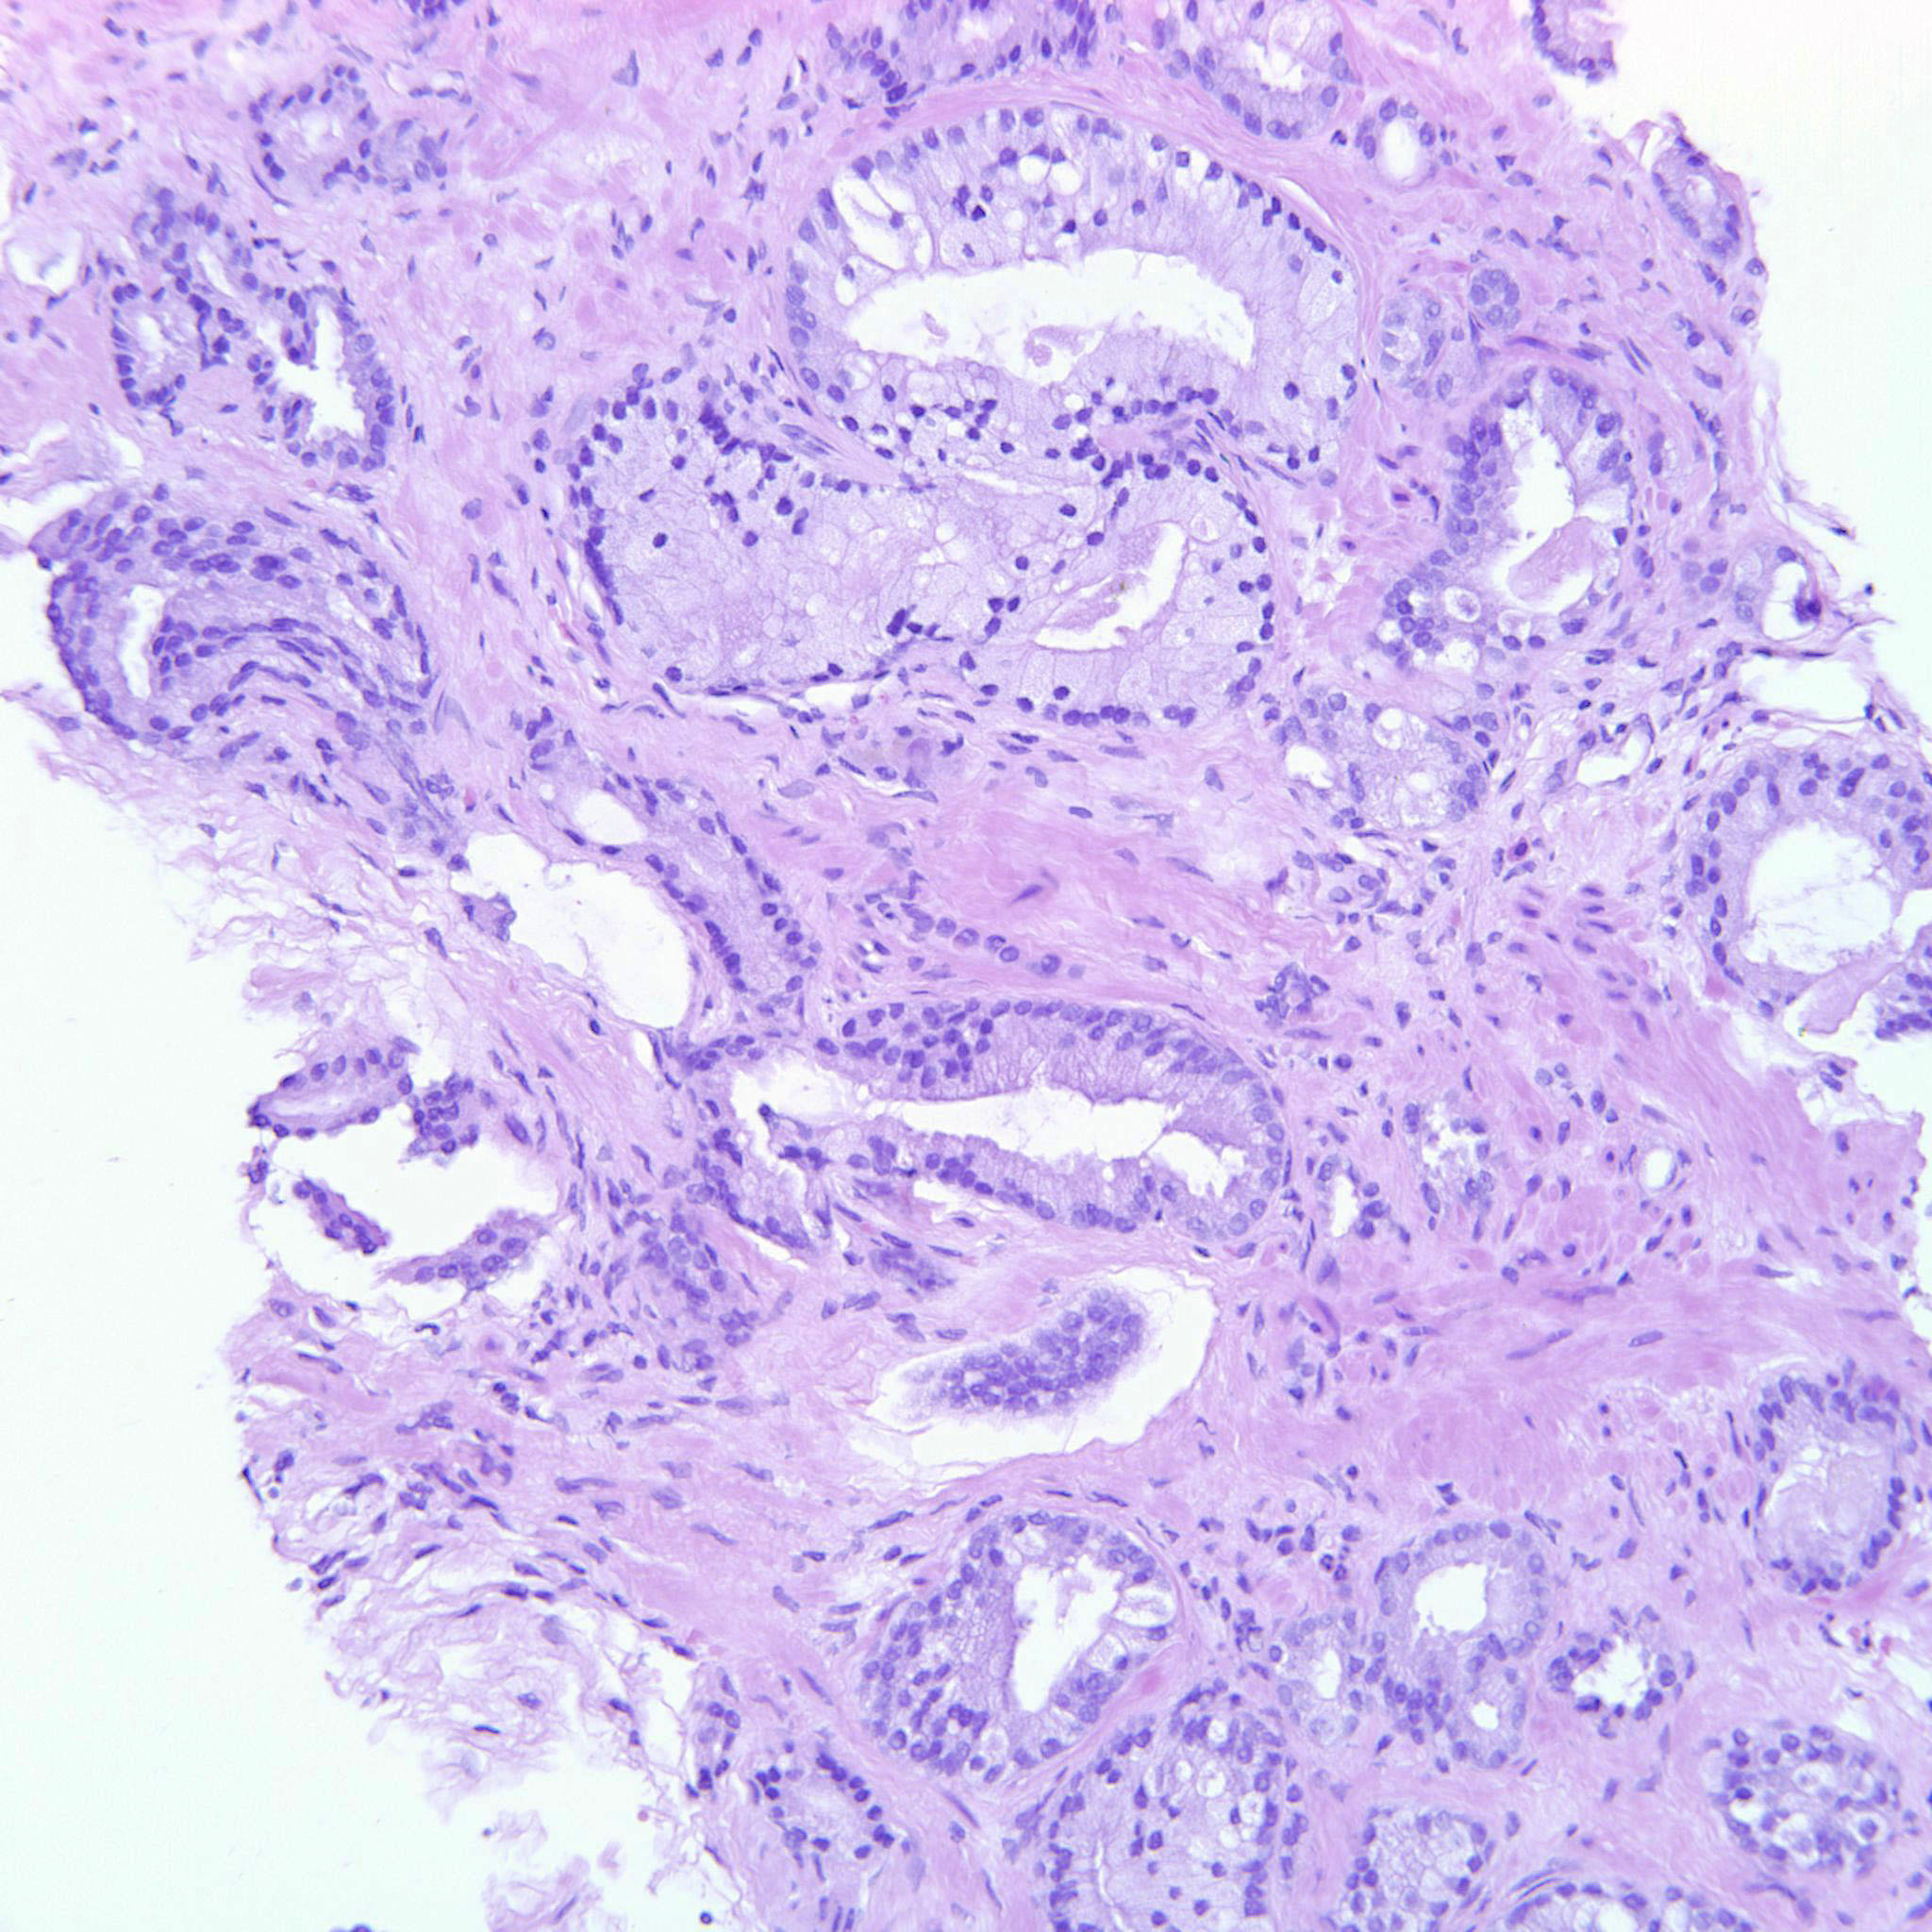

Prostate cancer grading

Case ID: 699